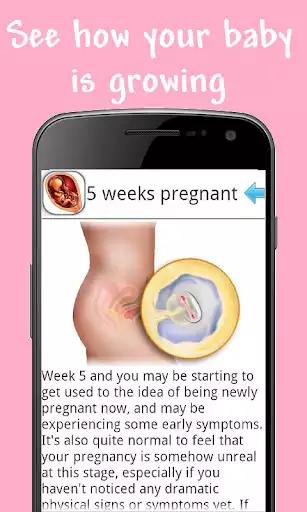

-- mother pregnancy week by week in step by step and stages this feature shows some quick information about you baby including size weight fetus age and some tips and helps track your progress in a countdown like fashion from a to z also included are some exercises to cope with the pain and symptoms

--- baby week by week development before birth and calculator in this tab you will more tips and help and about baby progress app also included are real ultrasound and high quality images